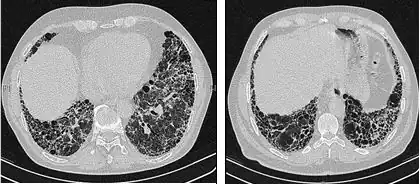

As radiografias de tórax são úteis na rotina de acompanhamento de pacientes com FPI. Infelizmente, as radiografias simples de tórax não são diagnósticas, mas podem revelar volumes pulmonares reduzidos, geralmente com marcas intersticiais reticulares proeminentes próximas às bases pulmonares.[3]

A avaliação radiológica por meio da TCAR é um ponto essencial no caminho do diagnóstico da FPI. A TCAR é realizada usando um scanner tomográfico axial computadorizado convencional sem injeção de agentes de contraste. As fatias de avaliação são muito finas, de 1 a 2 mm.

A TCAR típica do tórax da FPI demonstra alterações fibróticas em ambos os pulmões, com predileção pelas bases e pela periferia. De acordo com as diretrizes conjuntas das ATS, ERS, JRS e ALAT de 2011, a TCAR é um componente essencial da via diagnóstica na FPI, que pode identificar a PIU pela presença de:[3]

- Opacidades reticulares, geralmente associadas a bronquiectasias de tração

- Favos de mel manifestados como espaços aéreos císticos agrupados, geralmente de diâmetros comparáveis (3-10 mm), mas ocasionalmente grandes. Geralmente são subpleurais e caracterizados por paredes bem definidas e dispostos em pelo menos duas linhas. Em geral, uma linha de cistos não é suficiente para definir os favos de mel.

- Opacidades de vidro fosco são comuns, mas menos extensas do que a reticulação.

- Distribuição caracteristicamente basal e periférica, embora muitas vezes irregular.

Tomografia computadorizada de alta resolução do tórax de um paciente com FPI. As principais características são um padrão periférico, predominantemente basal, de reticulação grosseira com favos de mel